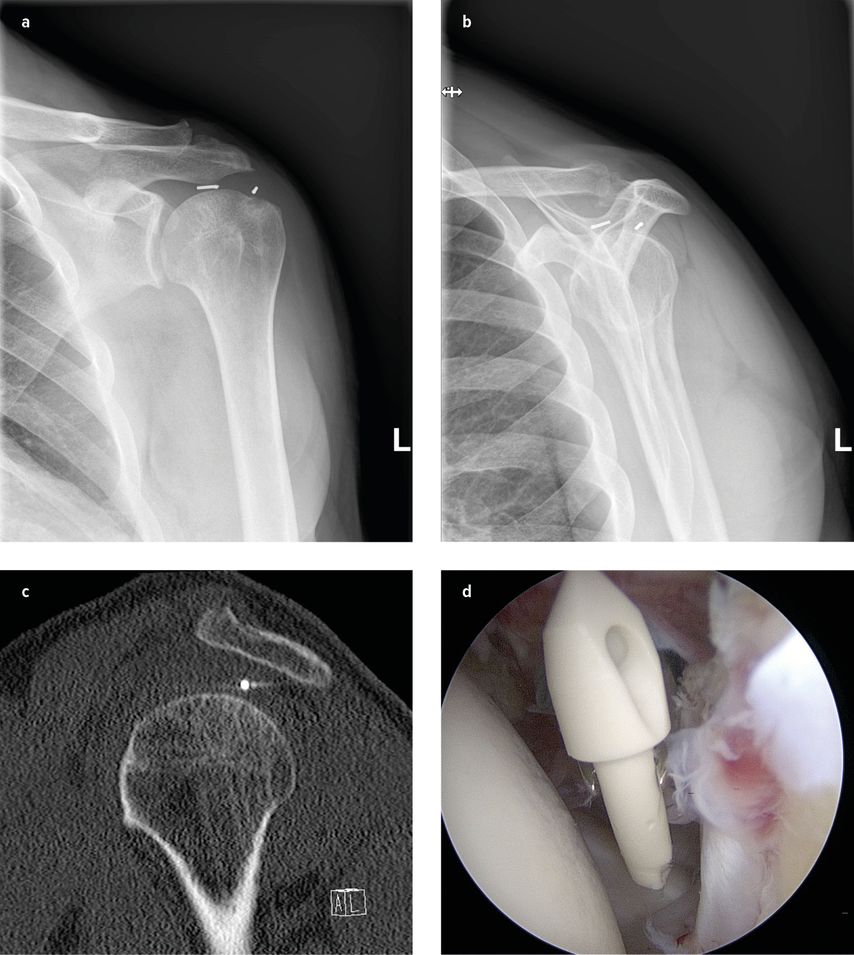

Abb. 1:Röntgen in 2 Ebenen und CT einer Reruptur mit disloziertem Anker und intraoperativer arthroskopischer Implantatentfernung

Die präzise Analyse der zugrunde liegenden Pathologie ist entscheidend für die Planung eines erfolgreichen Revisionseingriffs nach Rotatorenmanschettenrekonstruktion. Eine umfassende Diagnostik umfasst eine detaillierte Anamnese, eine gründliche klinische Untersuchung sowie den gezielten Einsatz bildgebender Verfahren.33, 34 Das Vorliegen einer Pseudoparese weist klinisch häufig auf eine Reruptur hin.

Röntgenaufnahmen: Standardmäßig werden Röntgenaufnahmen der Schulter in drei Ebenen angefertigt, um den knöchernen Zustand, die Gelenkskongruenz sowie das Vorhandensein und die Position des Implantats zu bewerten.

Eine Erweiterung erfolgt gegebenenfalls per Computertomografie (CT) oder CT-Arthrografie.